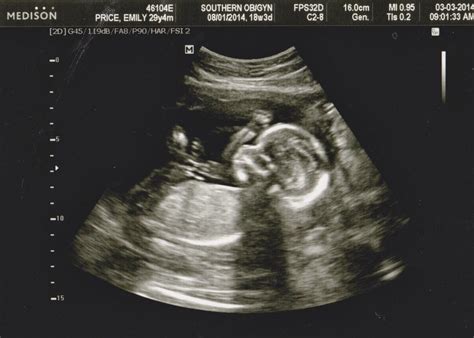

• Baby's Measurements: The ultrasound will provide measurements of your baby's head circumference, abdominal circumference, and femur length. These measurements help assess your baby's growth and development.

• Anatomy Scan: This detailed scan checks for any structural abnormalities in your baby's organs and systems. It includes a thorough examination of the heart, brain, spine, kidneys, and other vital organs.

• Placenta and Amniotic Fluid: The ultrasound will also evaluate the position and health of the placenta, as well as the amount of amniotic fluid surrounding your baby.

• Gender Determination: If you wish to know your baby's gender, this ultrasound is often the earliest time when it can be determined with reasonable accuracy. However, it's important to note that the accuracy can vary.